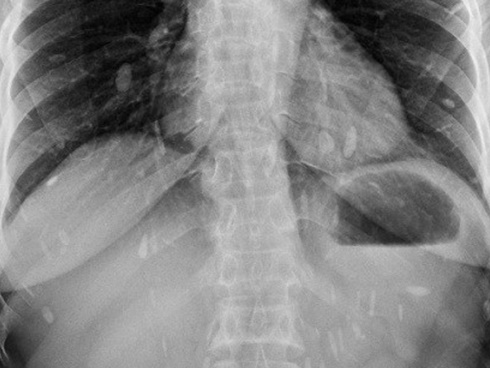

Sán lá gan có mặt ở các loại rau sống, gói cá, thịt sống...